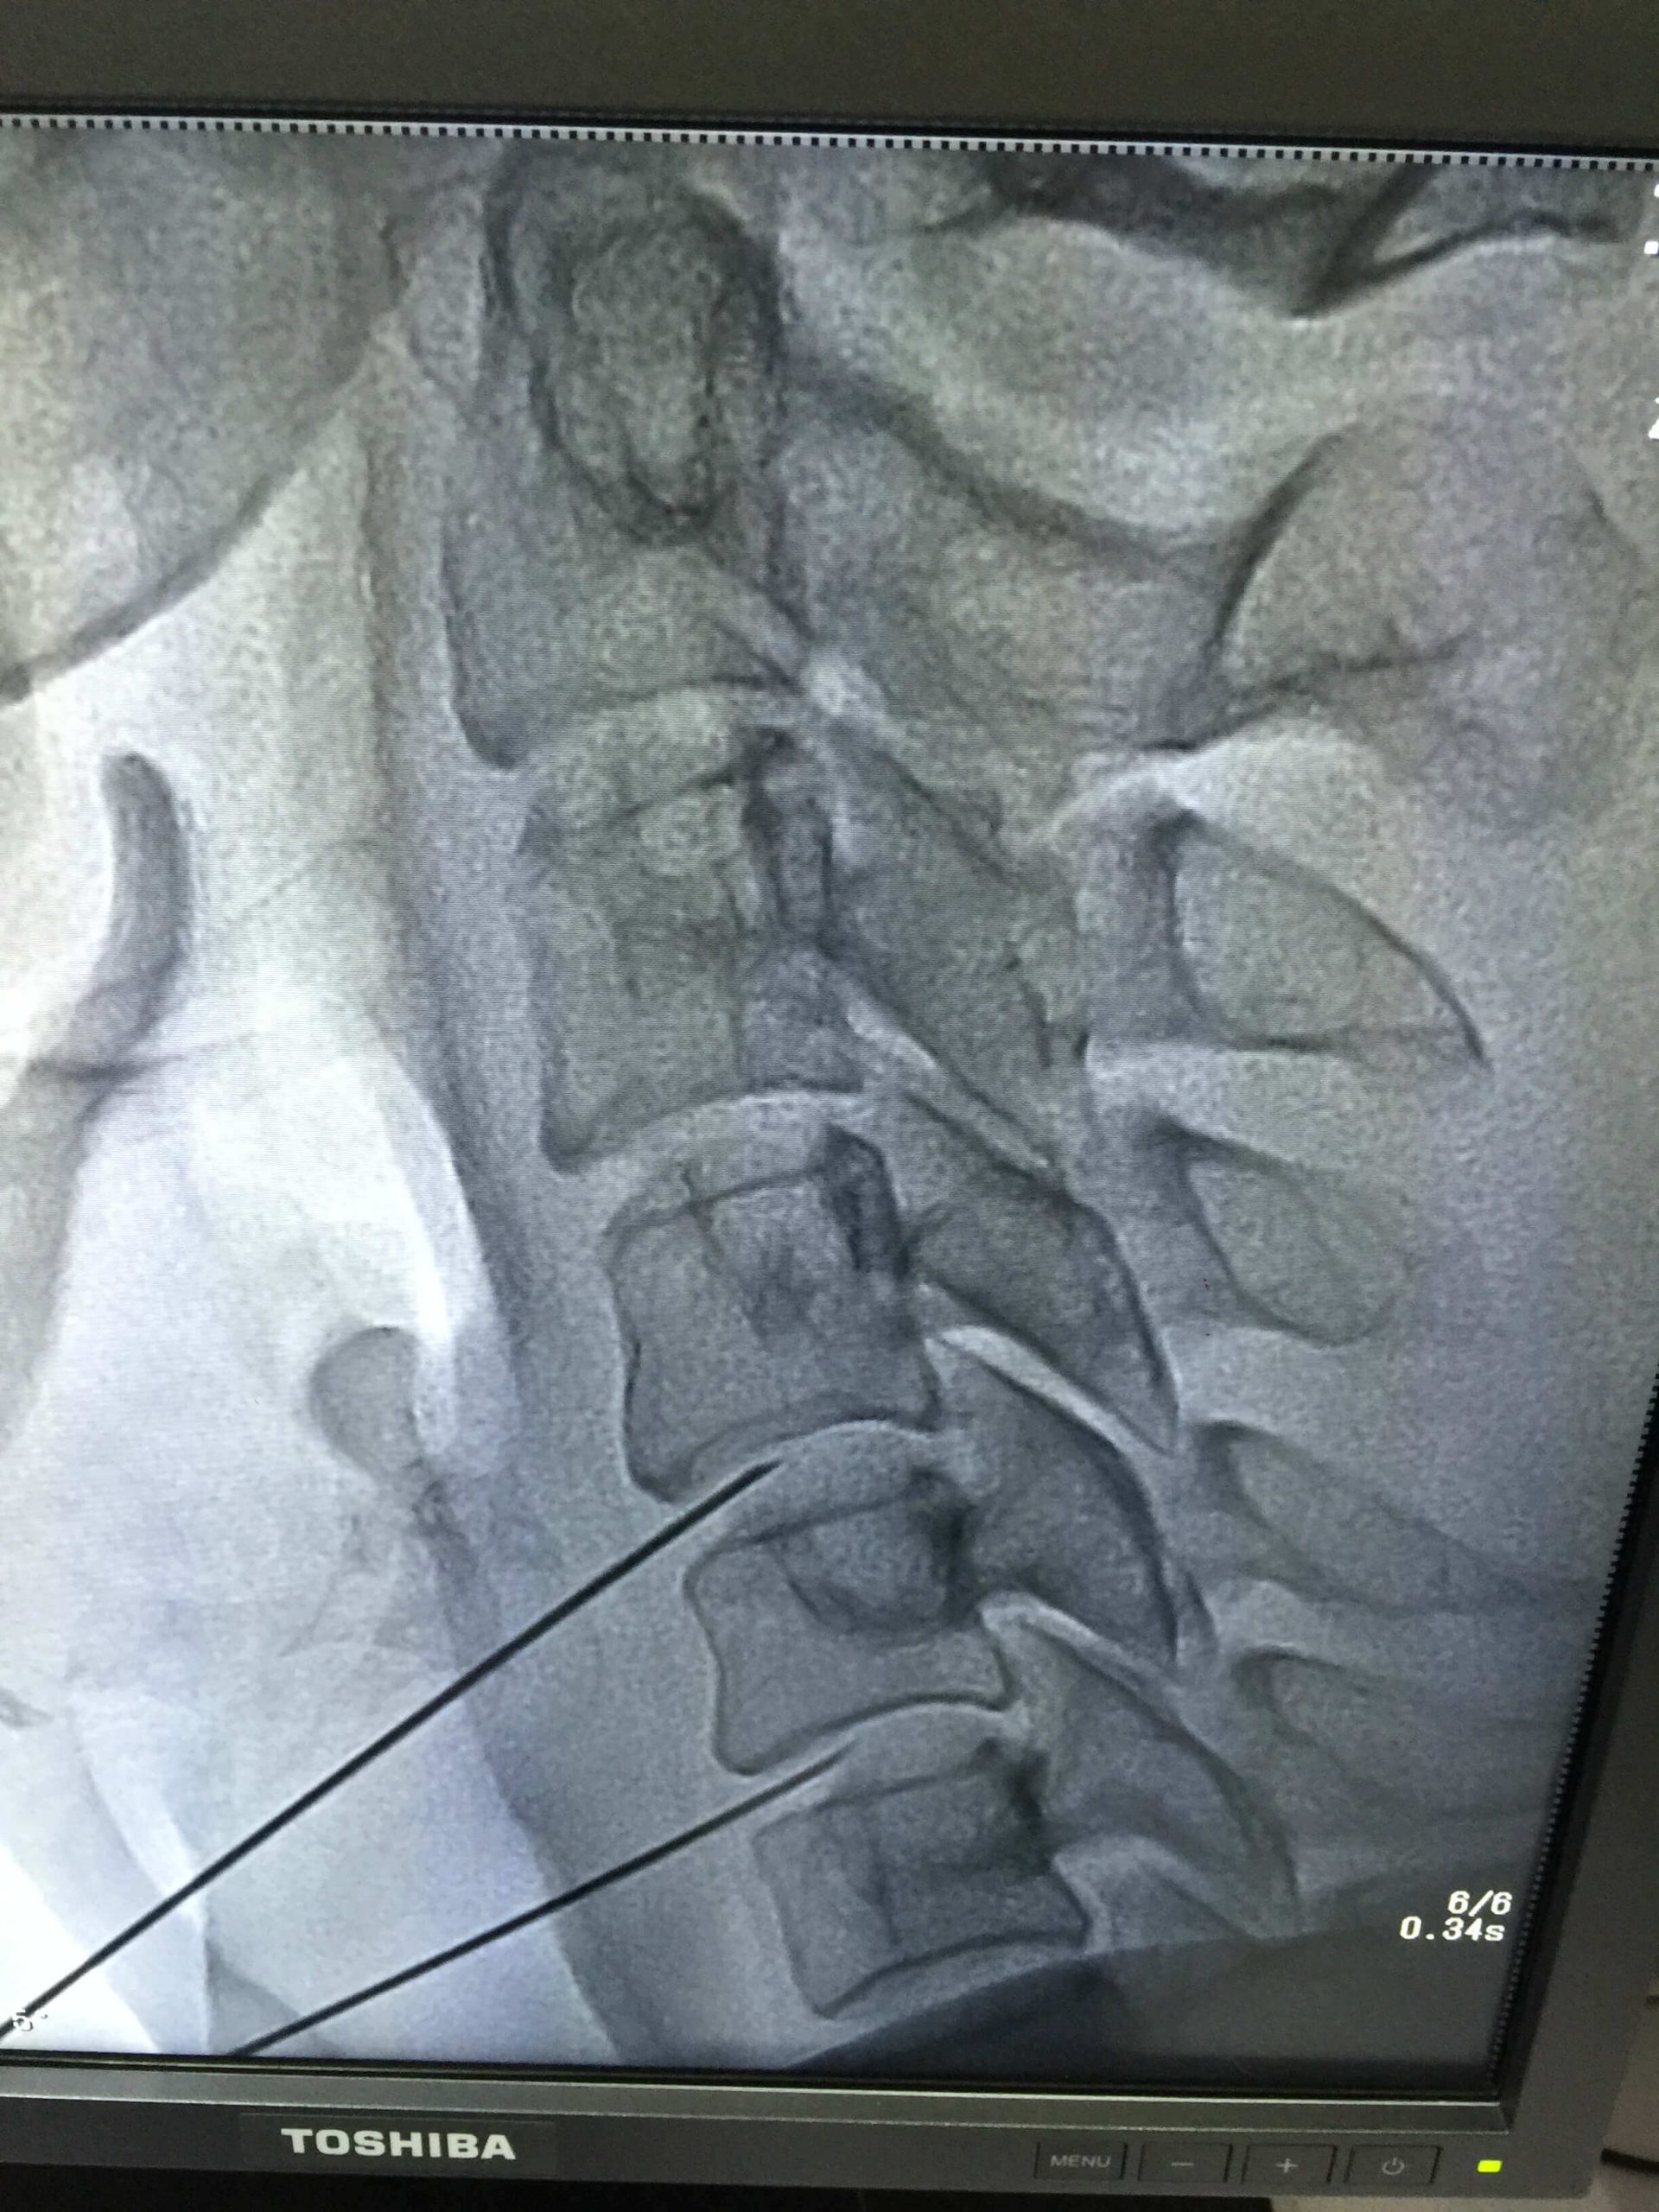

Ozone Therapy (Disc Problems) Overview

Ozone therapy is an innovative treatment that has shown promising results in treating disc problems. This therapy involves injecting ozone gas into the affected area to reduce inflammation and improve blood circulation, thereby promoting the natural healing process. The benefits of ozone therapy are numerous and it is considered an excellent and safest alternative to traditional treatments such as surgery or medication. With its non-invasive approach, it is becoming a popular choice among patients seeking long-lasting relief from disc problems. If you are interested in exploring ozone therapy as a treatment option, please consult with a licensed healthcare professional before proceeding. Their expertise will be key in determining the most effective course of action for your unique case.

Health Tips & Info